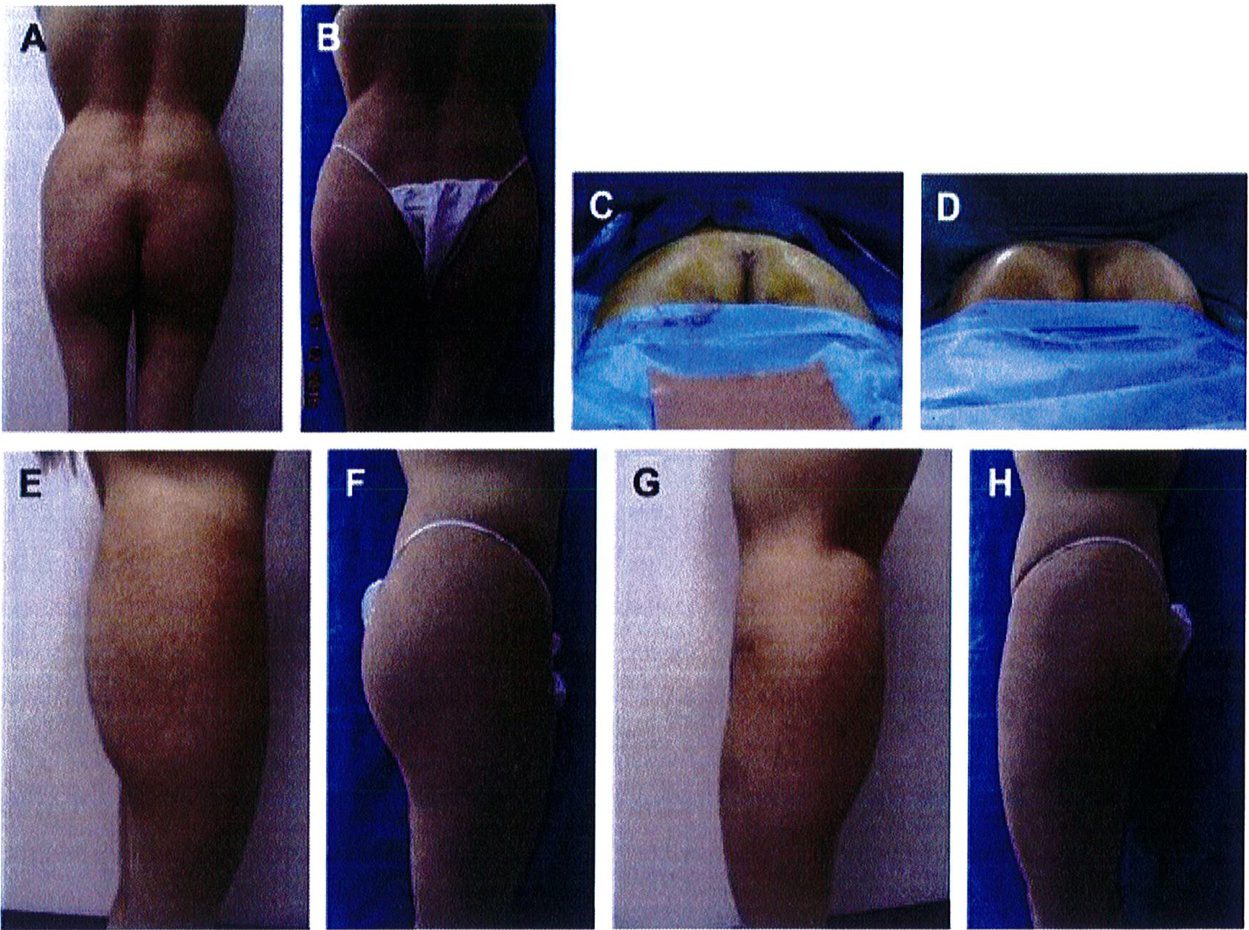

Kết quả phẫu thuật quan sát trên Hình. 3-5.

Hình. 3. (A-H) Tiền phẫu, chu phẫu và sau hậu phẫu 6 tháng của một bệnh nhân nữ 38 tuổi đươc ghép túi đôn mông với thể tích 330 cm3.